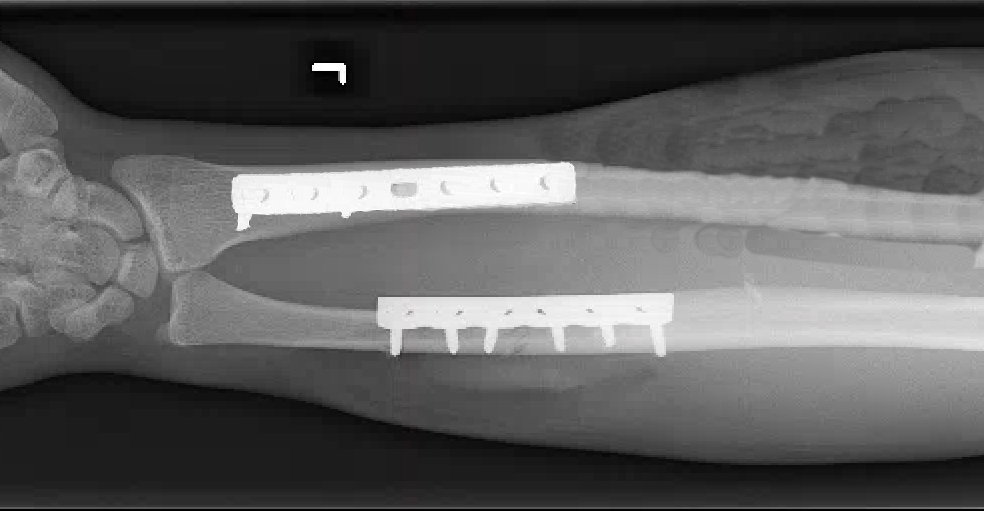

- Also known as a reverse Monteggia fracture or Piedmont fracture, the Galeazzi fracture is fracture of the middle to distal third of the radial shaft combined with a subluxation or dislocation of the DRUJ.8,11

- These injuries typically result from direct impact to the radius with forearm pronation. When a patient sustains a radial shaft fracture in the middle to distal third of the bone, suspicion should be raised for an associated DRUJ injury.1,8

Imaging11

- Radiology studies - X-ray

- Anteroposterior (AP) and lateral views are usually sufficient, but an oblique view may help to better classify the injury.

- If a coexistent injury is suspected, the distal wrist and proximal elbow should also be radiographed.